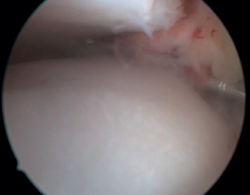

El PAT óseo por osteofitos también ha sido relacionado con la presencia de inestabilidad crónica. Se ha postulado que la alteración en la cinemática articular secundaria a la insuficiencia ligamentosa favorece el desarrollo de osteofitos en la región anterior de la tibia y el astrágalo(36,37). Estudios recientes han cuestionado la teoría de tracción capsular repetida como origen de los osteofitos en la práctica deportiva(38), ya que es fácilmente demostrable que los osteofitos se localizan intraarticulares por dentro de la inserción capsular, en el contexto de una artroscopia de tobillo (Figura 2). Por ello, la artroscopia con dorsiflexión de tobillo es fundamental para poder resecar los osteofitos de forma segura sin daño capsular ni a las estructuras suprayacentes, mientras que la técnica clásica de tracción (invasiva o no) dificultaría enormemente su resección, por lo que hoy en día se desaconseja su uso rutinario(3,39). Vega distingue dos tipos de osteofitos(3), según sean por trauma repetitivo (forma de pico) o por inestabilidad (en forma de visera). El concepto de microinestabilidad se asocia a microtraumatismos de repetición que podrían ser el origen de osteofitos con esta morfología característica (Figura 3).

Figura 3. Osteofito por inestabilidad crónica. A: el osteofito conforma un tope óseo que se extiende en el borde anterior del plafón tibial y la cara anterior del maléolo medial; B: imagen artroscópica.